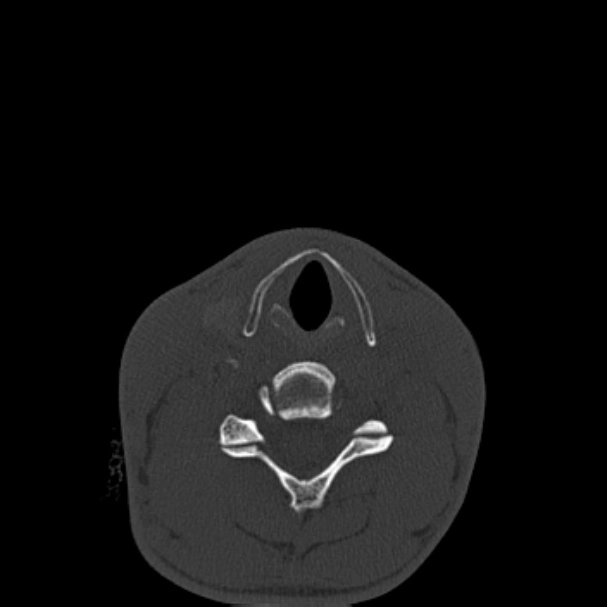

• Gãy xương phức tạp

Gãy xương Le Fort (Le Fort fracture classification)